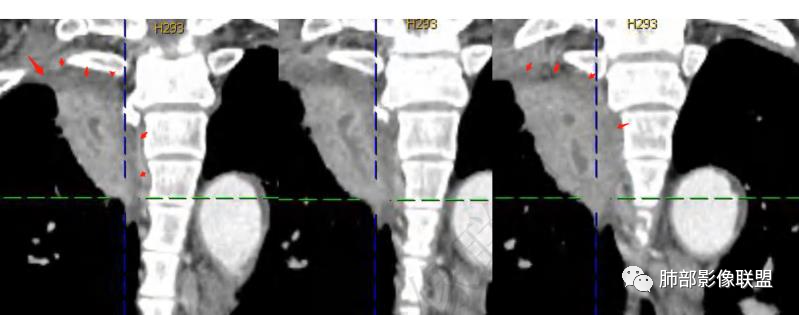

良孑:右上肺占位,有平直及u型凹陷,其内见粘液拴及虫蚀样坏死空洞,不均匀强化,坏死空洞环状强化,失状位病灶沿支气管长轴生长呈爬行征样改变,综合考虑为炎性肉芽肿,首选TB,鉴别诊断鳞癌

琦遇:病灶沿右肺上叶尖段走形实变,远端大近端小,边缘平直收缩为主,近端尖段分支部分截断,内部可见扩张的支气管粘液栓,增强后明显强化,比较均匀,内部血管走形自然,与纵膈胸膜及后胸膜呈糊墙样,未见栽桩,纵膈未见明显肿大淋巴结 综合分析考虑炎性病灶可能性大 (IMT、OP、结核、慢性炎症) 因患者年龄大、老烟民 警惕恶性可能(淋巴瘤、鳞癌) 临床上下一步做支气管镜看看

谢加平:右肺上叶尖后段见长斑块实变影,边缘清楚,有平直征,渐进性明显强化及分布血管影自然,肿块内见连续未强化粘液栓,肺门侧引流支气管征,相应肺段支气管内壁环形增厚(肉性特点),肿块周边索条纤维化,及胸膜反应性增厚,综合方向炎性肉芽肿,常规抗炎诊断两周复查,注意结核性肉芽肿,建议支气管镜肺泡灌洗及肺穿刺活检。

张延军:右肺上叶条片影,边缘以平直及凹陷为主,病灶内见管状低密度影,延迟后边缘有强化,近段气管截断,血管走形自然,整体外宽内窄,考虑炎性肉芽肿,结核不除外

右上叶尖段带状实变影

外围大、内带小,宽基底与胸膜相连,附近卫星灶

支气管进入病灶内,广泛胸膜增厚

支气管粘液栓

支气管堵了,但是远端粘液栓:是粘液栓堵塞?还是狭窄或堵塞后继发粘液栓?

病灶是支气管腔内堵塞导致远端实变、不张?还是外围病灶融合、实变影响近端支气管?

整体考虑肿块应该不支持,因为支气管、血管走形还算自然,只是收缩在一起,如果肿块走形不会这么自然,会推移、变形,侵犯

现有的图显示近端支气管还是连续的,只是远端扩张,腔内粘液栓,其实还应当看重建的支气管连续的图,与近端含气部分的连续